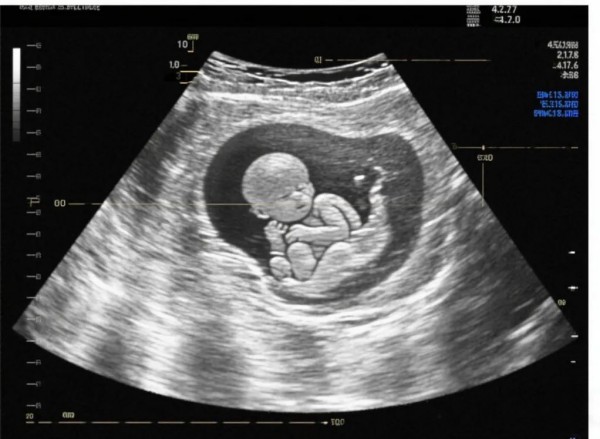

孕期四维彩超里的“小个性”:宝宝配合度大揭秘

孕期做四维彩超,是准妈妈与胎宝宝的初次见面,在这过程中,有的宝宝乖巧配合,快速展现萌态,有的却调皮捣蛋,让检查一波三折

宝宝配合度不同,原因藏在多个方面。从孕周来看,孕 22 - 24周左右羊水适量、胎儿大小适中、活动空间充足,多数宝宝状态好,易配合。但孕周过早,宝宝发育尚不完善,器官成像不清;过晚,空间拥挤,宝宝蜷缩着就不太乐意转身、抬手。胎儿自身性格也有影响,有些天生好动,检查时小手乱挥、频繁翻身,可以让B超医生更清楚地看到胎儿各个部位。有的则文静些,静静躺着,医生则很难拍到胎儿的某些部位。

四维彩超能够监测到胎宝宝的健康情况,对胎儿进行从头到脚系统性检查,可初步筛查胎儿九大类畸形及部分其它明显畸形,是孕期最重要的一次超声检查: